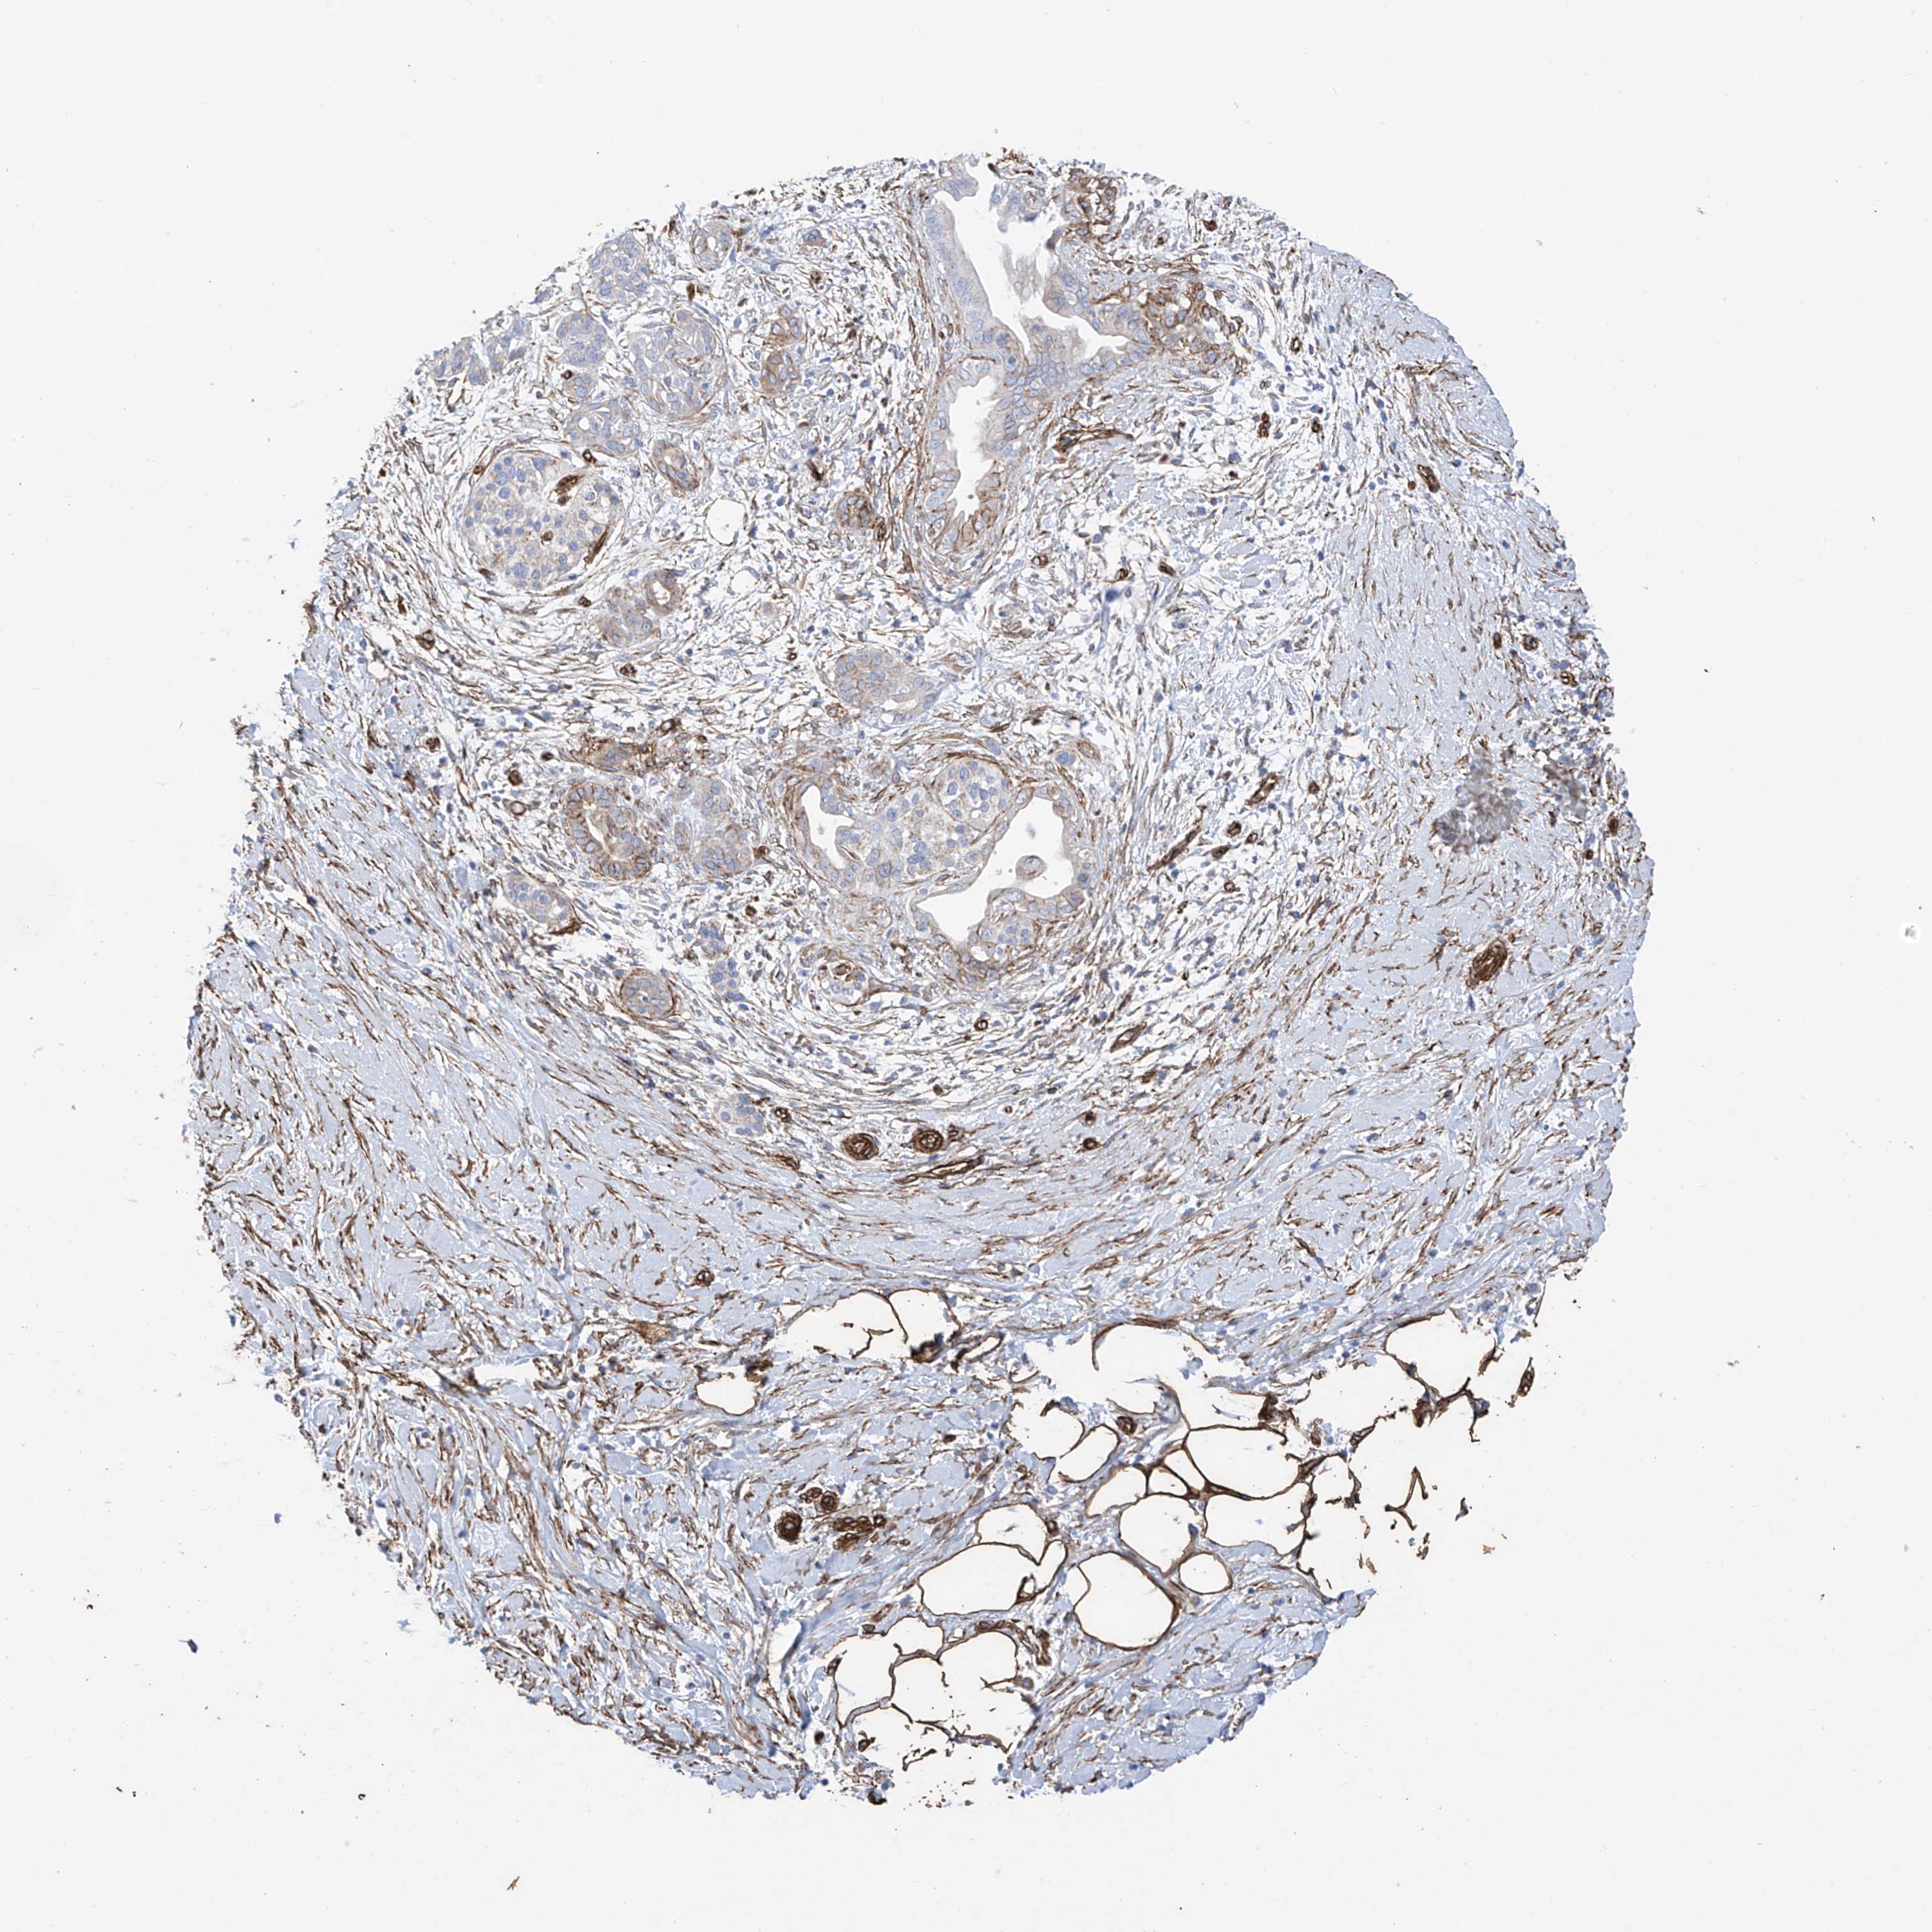

PANCREATIC CANCER - Protein expressioni

A mouse-over function shows sample information and annotation data. Click on an image to view it in a full screen mode. Samples can be filtered based on level of antibody staining by selecting one or several of the following categories: high, medium, low and not detected. The assay and annotation is described here.

Note that samples used for immunohistochemistry by the Human Protein Atlas do not correspond to samples in the TCGA dataset.

Antibody stainingi

Antibody staining in the annotated cell types in the current human tissue is reported as not detected, low, medium, or high, based on conventional immunohistochemistry profiling in selected tissues. This score is based on the combination of the staining intensity and fraction of stained cells.

Each image is clickable and will lead to virtual microscopy that enables deeper exploration of all samples and also displays staining intensity scores, fraction scores and subcellular localization as well as patient and tissue information for each sample.

Antibody HPA034825

Staining

High

Medium

Low

Not detected

Intensity

Strong

Moderate

Weak

Negative

Quantity

>75%

75%-25%

<25%

None

Location

Nuclear

Cytoplasmic/membranous

Cytoplasmic/membranous,nuclear

Adenocarcinoma, NOS